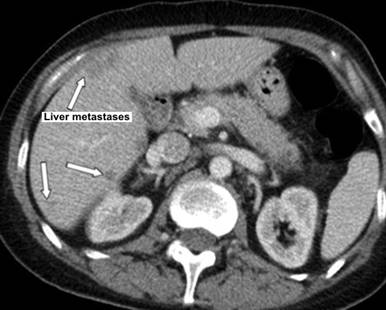

Figure 3. Several liver lesions initially reported as hemangiomas but subsequent checking confirmed liver metastases. |

Ultrasound and subsequent computerized tomography (CT) showed no gallstones but CT showed liver lesions which were reported initially as hemangiomas. On the 9th day of admission she developed swollen left upper limb. At that stage the radiology imaging were reviewed at the radiology multidisciplinary team meeting and her chest X-ray was compared to the previous one of two months which showed significant mediastinal widening and chest CT was suggested and showed extensive mediastinal disease and left internal jugular vein thrombosis and compression of left subclavian vein (Figures 1-4). The radiologist suggested lymphoma as the primary malignancy; however, the bone marrow biopsy showed a cellular marrow extensively infiltrated by a high-grade malignant tumour composed of small cells with scanty cytoplasm. Numerous mitoses were seen. Immunocytochemistry demonstrated a strong positive reaction for CD56 and bcl2, while a focal positive reaction was seen for bcl6. Perinuclear dot positivity was seen for MNF116. A negative reaction was seen for CD79, CD20, CD34, CD23, CD10, CD5, CD3 and cyclin D1.

Initial radiology report put less weight on the liver lesions; however, reviewing imaging and the commitment to find the cause of hypercalcemia in this case has helped to reach the definite diagnosis.